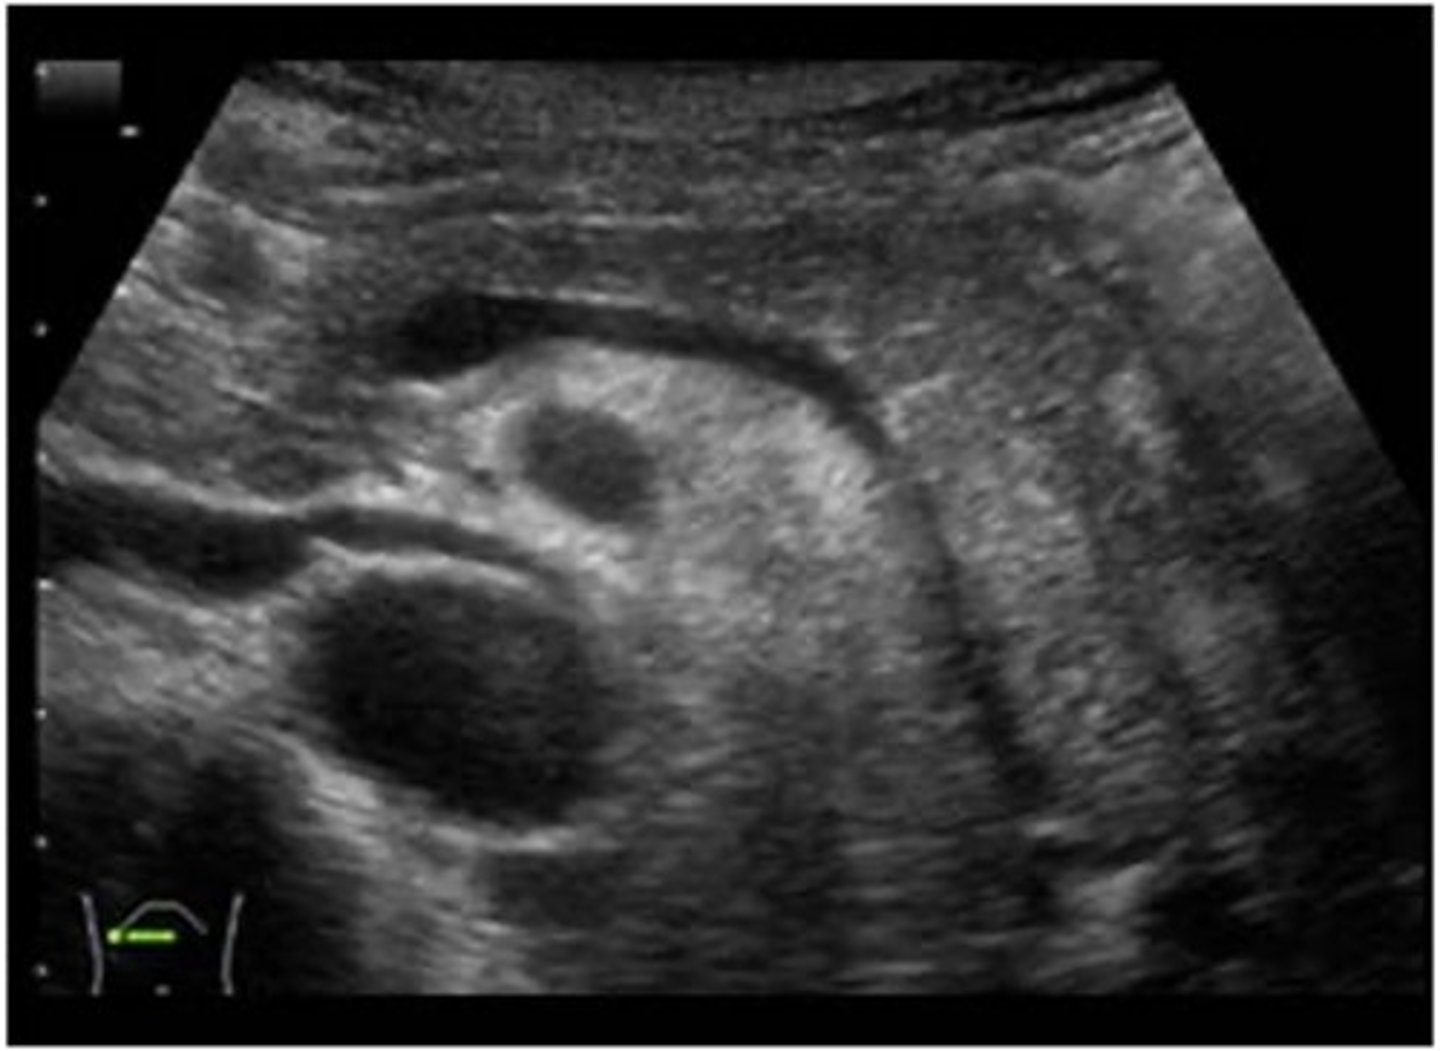

Right lobe of liver and hepatic veins on US

right lobe of liver and kideny on US